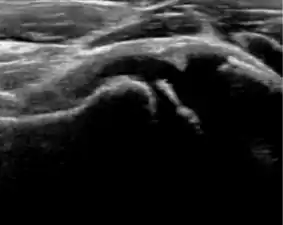

During childhood, ultrasound is a quick method to assess hip pain and quite often may be used to avoid use of irradiating techniques, such as radiography or CT. Ultrasound allows evaluation of joint effusion, synovial thickening and neovascularity, the bone/cartilage contour, and the femoral head-neck alignment. Although sonography is extremely sensitive in detecting increased synovial fluid, it is nonspecific and cannot be used with accuracy to determine the type of fluid. Transient synovitis of the hip, despite being the most frequent cause of pain in children between 3 and 10 years, remains a diagnosis of exclusion. It usually shows anechoic fluid, but echogenic fluid can also be found. The effusion is considered pathologic when it is measured at >2 mm in thickness. The differential diagnosis is wide, including osteomyelitis, septic arthritis, primary or metastatic lesions, LCPD, and SCFE. Discrimination from septic arthritis is challenging, often requiring joint aspiration. In septic arthritis, US is able to demonstrate a hip joint effusion, synovial thickening, and cartilage damage, although the appearances are nonspecific.[1]

A step between the head and the physis can be detected in children with SCFE, while abnormalities in the femoral head contour may suggest the presence of LCPD. In both cases, radiographs are mandatory to confirm diagnosis and severity (Figure 12).[1]

Figure 12:

Normal ultrasound appearance of the femoral head-neck junction. -

Joint effusion in transient synovitis of the hip. -

Flattening of the femoral head in a patient with Perthes disease. -

Step in the femoral head-neck junction in a patient with SCFE.